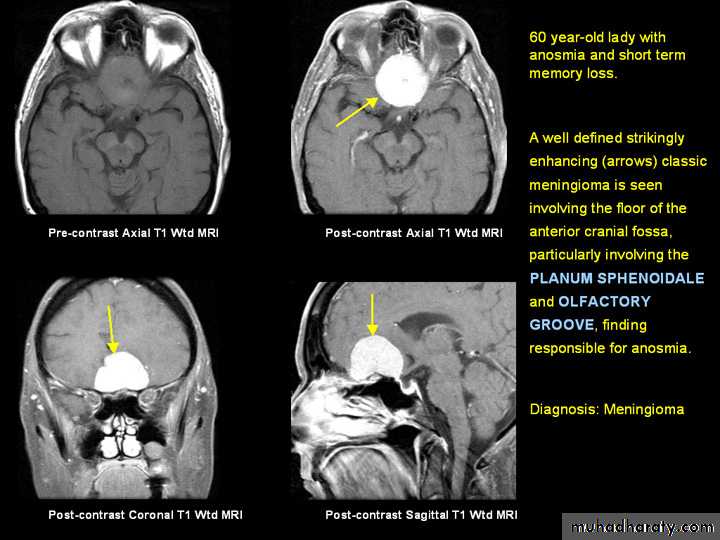

OLFACTORY GROOVE MENINGIOMA MRI’S